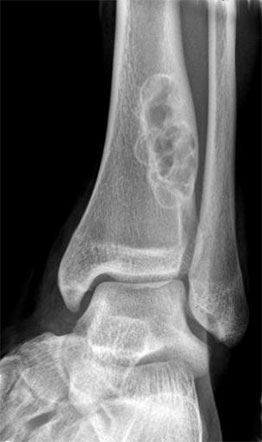

Опухоли костей являются редкими поражениями. Большая часть таких опухолей - доброкачественные образования, которые часто обнаруживаются случайно при радиологических исследованиях, проводимых по другим причинам. Что касается жалоб, они обычно проявляются отеком и болью. В редких случаях они обнаруживаются вследствие вызванного ими перелома в месте их расположения. Наиболее часто встречающимися доброкачественными образованиями являются остеоид-остеома, остеохондрома (экзостоз), энхондрома, неоссифицирующая фиброма, эозинофильная гранулема, простая костная киста, фиброзная дисплазия и внутрикостная липома / ганглия.